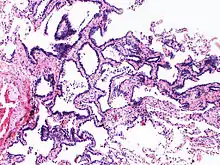

Image histologique de l'hyperplasie adénomateuse atypique.

L'hyperplasie adénomateuse atypique (HAA) est une lésion hyperplasique des pneumocytes bordant les alvéoles pulmonaires et présentant des anomalies cytonucléaires discrètes[1]. Ce terme est préconisé par l'Organisation mondiale de la santé dans sa classification des tumeurs de 2011, puis maintenu et précisé dans les versions de 2015 et 2021. Il caractérise une lésion glandulaire précurseur (précédemment dite lésion préinvasive) de très petite taille[2],[3].

Cette anomalie, de petite taille, inférieure ou égale à 5 mm[3], est une dysplasie, précancéreuse, précurseur de l'adénocarcinome pulmonaire in situ[4]. Le terme de carcinome bronchioloalvéolaire, autrefois employé pour décrire cette lésion est désormais abandonné[4].